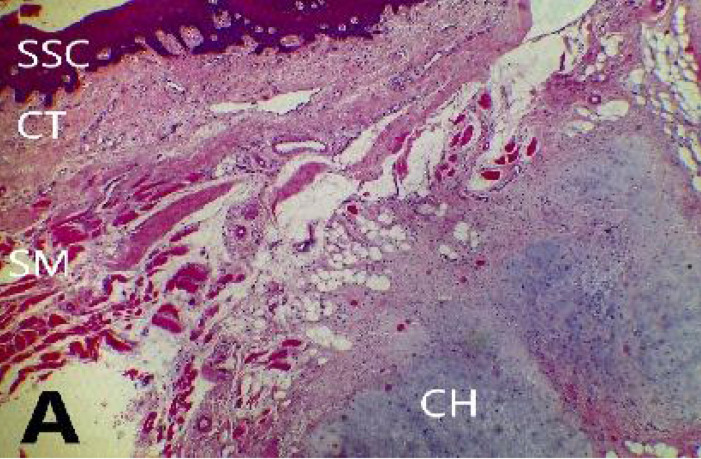

Background: Soft tissue cartilaginous choristoma (STC) is a mass of mature hyaline cells occurring in abnormal location. It is also referred to as extraskeletal choristoma; a rare lesion that frequently occurs on the tongue in orofacial region.The objective is to bring to the attention of Clinicians especially in secondary health care facilities the need of thorough investigations of tissue specimen to prevent misdiagnosis and avail themselves every diagnostic tool in the management of all oral swellings.

Case presentation: A 7-year old boy presented in Dental clinic in a secondary health care facility with history of an asymptomatic, non-tender and slow-growing swelling on the dorsum of the tongue of 3 years duration. Surgical excision was done under general anaesthesia. Histopathological and immunohistochemical evaluations were the tools used to establish its diagnosis.

Conclusion: Soft tissue choristoma is rare benign swelling that mostly occur in the anterior two-third of the tongue and can be misdiagnosed clinically but diagnostic tools like histopathology and immunohistochemistry will help confirm it.